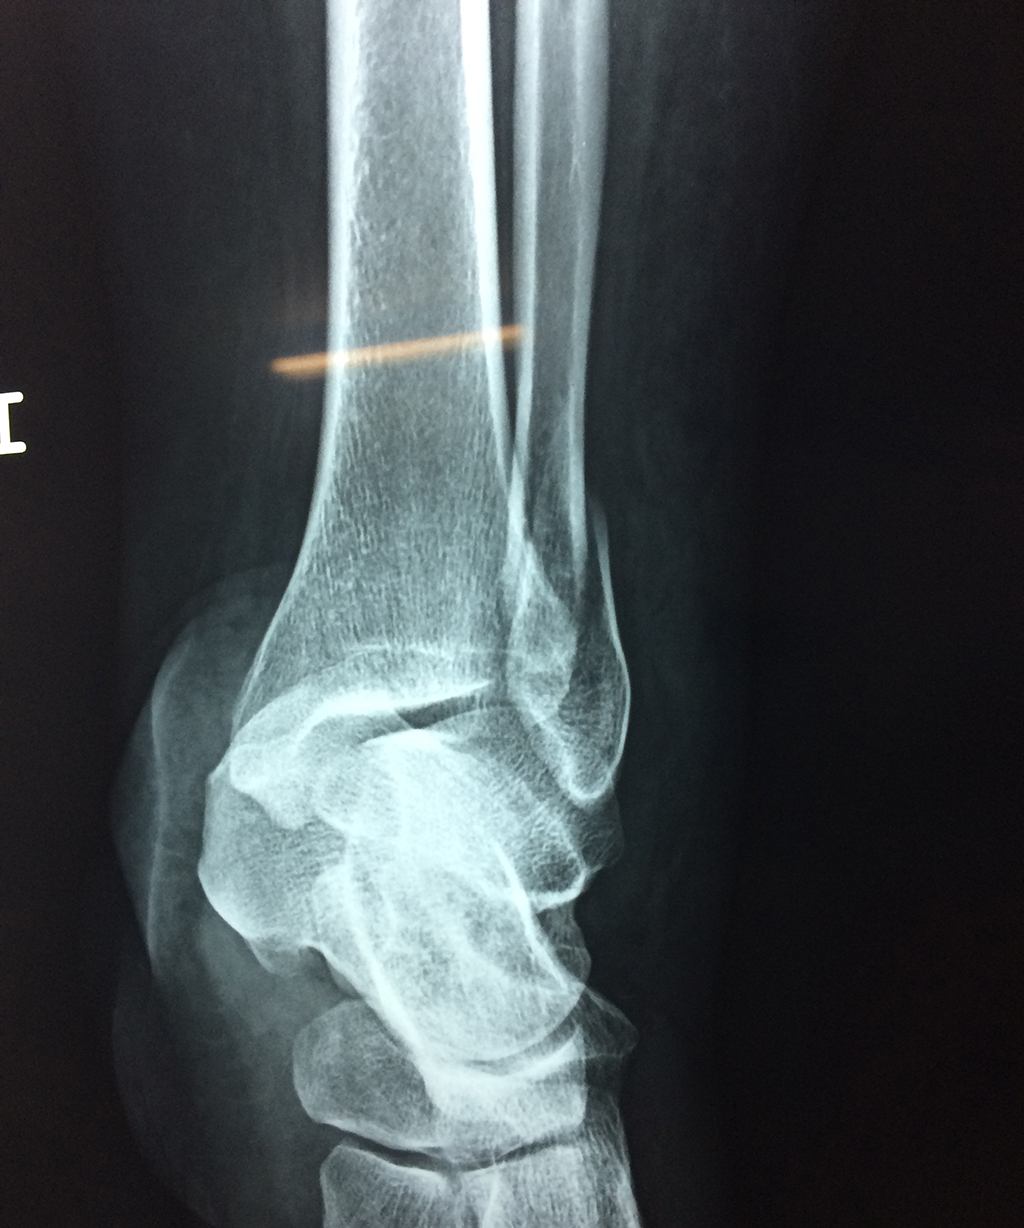

Una fractura de tobillo es la rotura de uno o más de los huesos del tobillo. Estas fracturas pueden ser:

- Los extremos de los huesos están desalineados entre sí (desplazados).

- La fractura se extiende hasta la articulación del tobillo (fractura intra-articular).